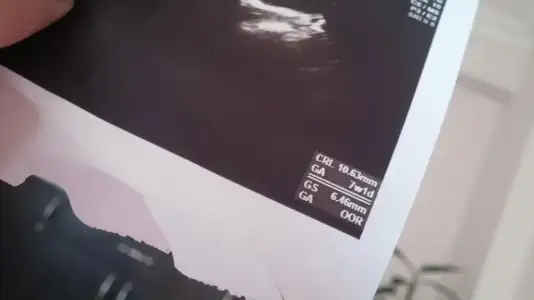

Kese olcusunu bimiyorumda kagitta yazarmi acabaKese ölçüsü ne dedi..ilk defa o gittin canm..

Kesende bebeginde belli canim gs kese crl bebek olcusu

tesekkur ederim canmKesende bebeginde belli canim gs kese crl bebek olcusu

Aa bilmiyrdum canm ben. Belli iyi mi ben anlamadim. Yalniz dis gebelik degil dedi

Ben çok anlamıyorum ama bebeği görse demezmiydi bu bebek diye..canm ne zaman. Gel dedi kalp atışı için...kese boyutun gayet iyi bence ..tesekkur ederim canm

Aa bilmiyrdum canm ben. Belli iyi mi ben anlamadim. Yalniz dis gebelik degil dedi

Tam çekersen bebegini net görebilirim belki kesenin icinde beyaz bişey var o bebek canim bebek belli olmasa orda ölçüsü olmazdi canim hayirlisiyla kucagimiza aliriz inşallahtesekkur ederim canm

Aa bilmiyrdum canm ben. Belli iyi mi ben anlamadim. Yalniz dis gebelik degil dedi